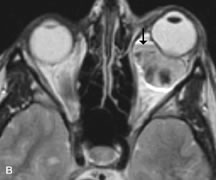

Lymphomas have MRI characteristics similar to those of inflammatory lesions in that they are hypointense to fat and isointense to muscle on T1-weighted images (Fig. 22). They may appear hyperintense to fat on T2-weighted images, perhaps owing to less fibrosis than that seen in orbital inflammatory pseudotumor, although this is not a consistent finding.31,50,66 Lymphoid tumors typically enhance moderately after contrast injection. Unfortunately, studies have shown that tumor density and homogeneity are similar between inflammatory and malignant orbital infiltrates, and MRI cannot differentiate these lesions.72,73

Fig. 22. A and B. T1- and (C) T2-weighted MR scans demonstrate a poorly defined multicompartmental mass enveloping the lateral rectus, superior rectus, and levator palpebrac superioris muscles. The lesion is isointense to brain on T1- and T2-weighted scans, as is typical for highly cellular neoplasms. D. Postcontrast fat-suppressed T1-weighted scan demonstrates intense enhancement of the infiltrating intraconal and extraconal tumor.